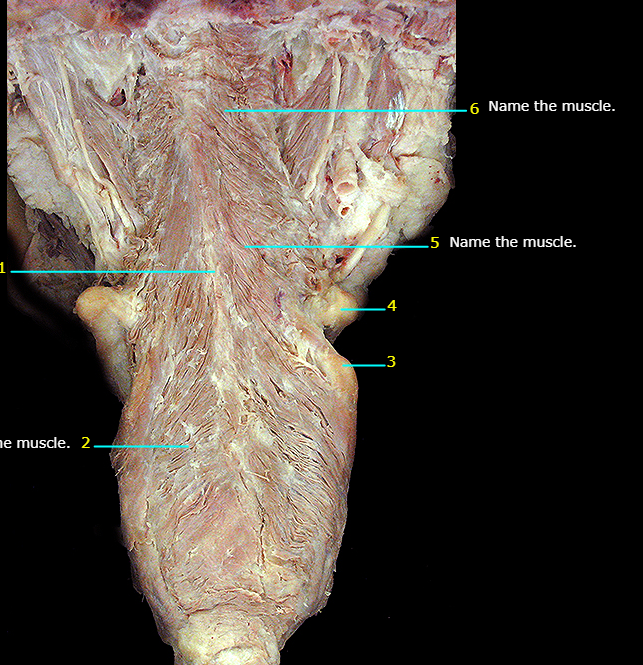

Name #6

Superior pharyngeal constrictor m.

Name #5

Middle pharyngeal constrictor m.

Name #2

Inferior pharyngeal constrictor m.

Name the muscle

Genioglossus m.

Hypoglossus m.

Styloglossus m.